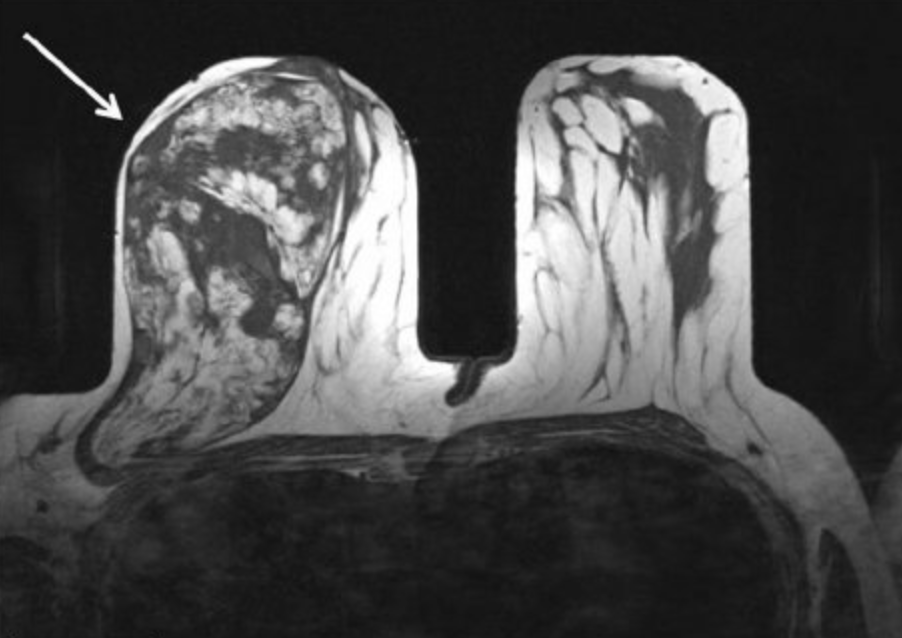

• Yet the radiologic appearance of hamartoma is characteristic and is said to resemble “breast within breast”

(a) and (b) – Digital mammograms, medio-lateral oblique (MLO) and cranio-caudad (CC) projections of the right breast showing an large ovoid, encapsulated mass lesion with a ‘breast ] within a breast’ appearance.